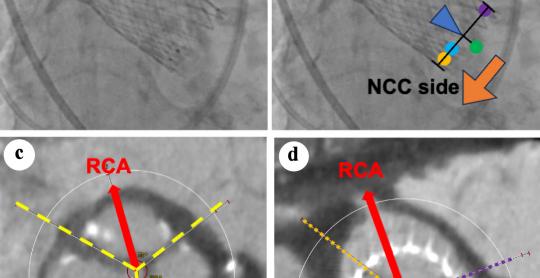

Cardiology Research

Vol. 16, No. 5, Oct 2025 pages 394-402

By Yusuke Kudo et al.